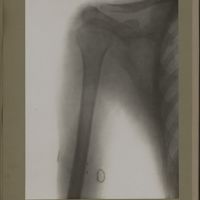

0115 - Page 3 - [Radiographie de l'humérus]0115 - Page 3 - [Radiographie de l'humérus]

0120 - Page 8 - [Radiographie de l'humérus]0120 - Page 8 - [Radiographie de l'humérus]

0193 - Page 81 - [Radiographie de l'humérus]0193 - Page 81 - [Radiographie de l'humérus]

0195 - Page 83 - [Radiographie de l'humérus]0195 - Page 83 - [Radiographie de l'humérus]

0202 - Page 90 - [Radiographie de l'humérus]0202 - Page 90 - [Radiographie de l'humérus]